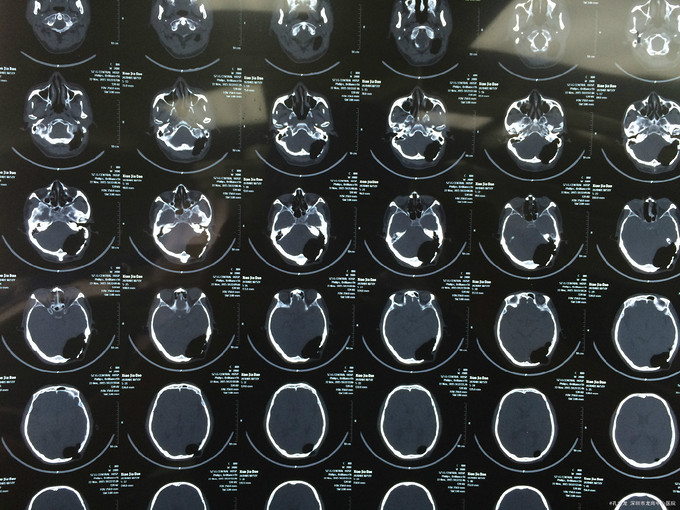

诊断:自发性颅内积气(张力性) 入院后予以完善相关检查,行颞骨乳突薄层CT扫面,考虑乳突气房内耳道漏气,粘膜瓣形成张力性气颅,再次开路手术创伤大,联合耳鼻喉科,行颅外手术,耳后入路磨除乳突气房,发现粘膜活瓣样活动,分辨漏气口,自取皮下筋膜,及带蒂肌皮瓣,填塞漏口及乳突气房,生物胶粘合,手术顺利,术后恢复良好。

患者恢复良好,术后未见皮下积气复发,复查头颅CT提示颅内积气明显吸收好转。对于此类自发性颅内积气,乳突气房与外界相通可能性大,开路手术创伤大,且效果不明显,联合耳鼻喉科手术效果明确,多学科合作在某些疾病的诊断及处理上非常重要。 颅内自发积气较少见,处理上的一点经验,跟大家一起分享,谢谢大家批评指教!